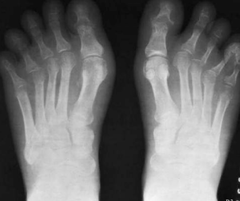

le cou

neck

le coude

elbow

j'ai deux

pieds

bras

jambes

le genou

knee

le pied

foot

les pieds

feet

les coudes

elbows

oreilles

les genoux

knees

la jambe

leg

la main

hand

le bras

arm

les mains

hands

les bras

arms

les jambes

legs